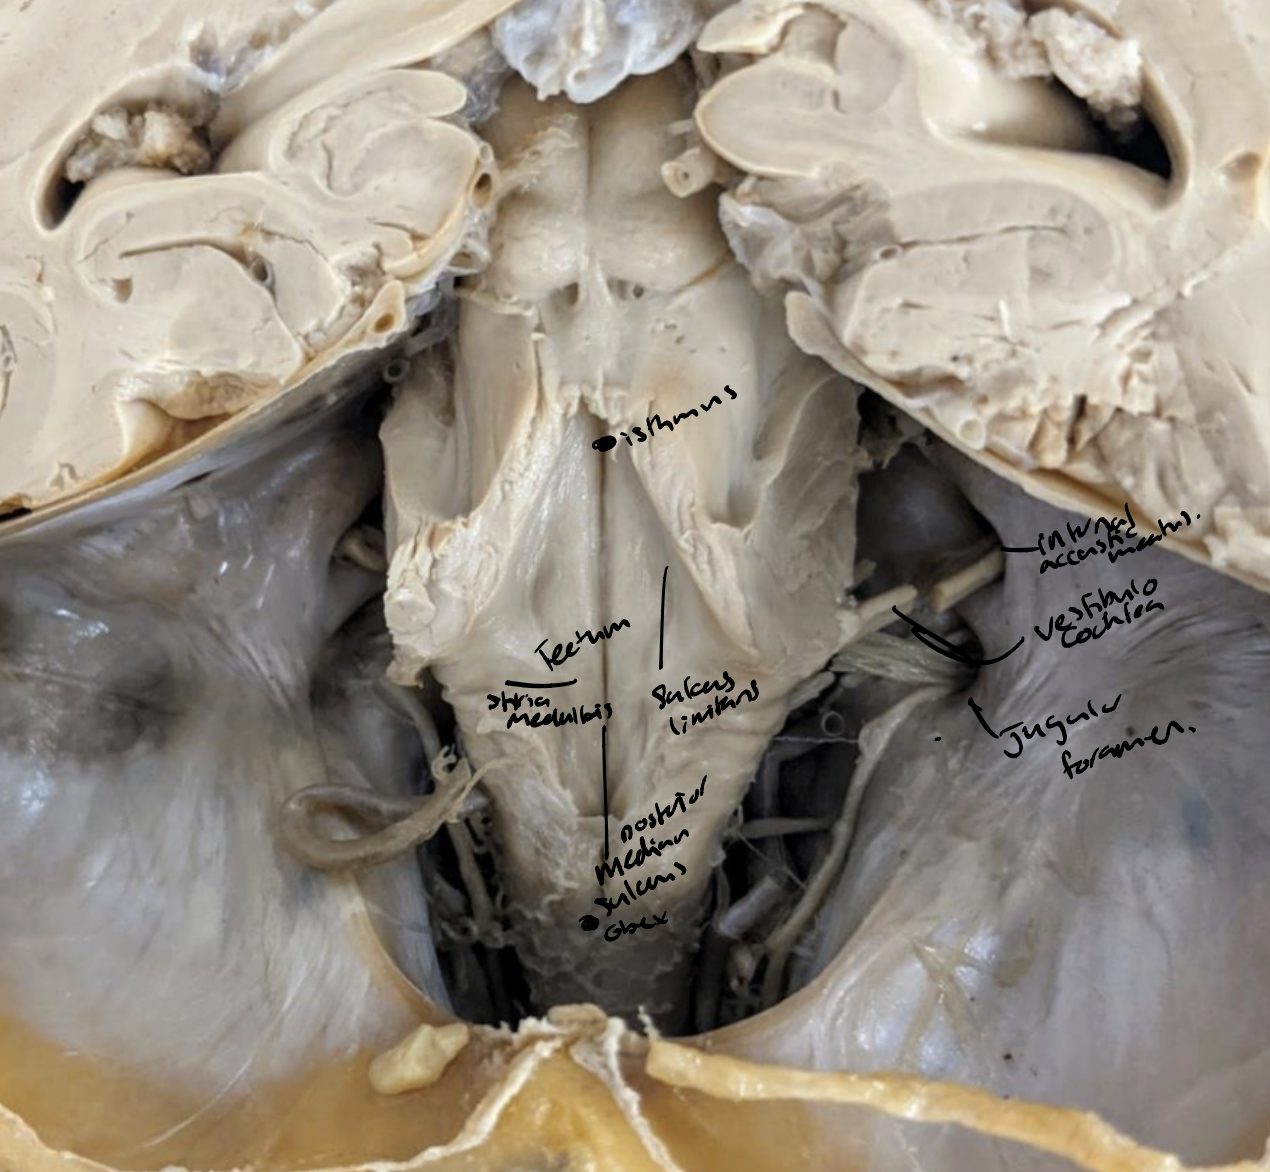

Striae medullaris thalami

Striae medullaris thalami